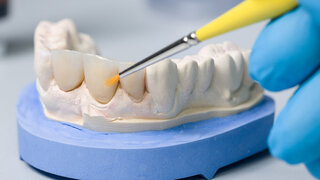

MedienrechtSocial Media: Vorsicht beim Teilen von Patientendaten! Zahnärzte nutzen Social Media auch, um mit klinischen Vorher-Nachher-Aufnahmen Werbung für die eigene Praxis zu machen. Wir haben die Rechtsanwältin Rebecca Richter gefragt, was erlaubt ist – und was nicht. 21.06.2021 PraxisZahnmedizin